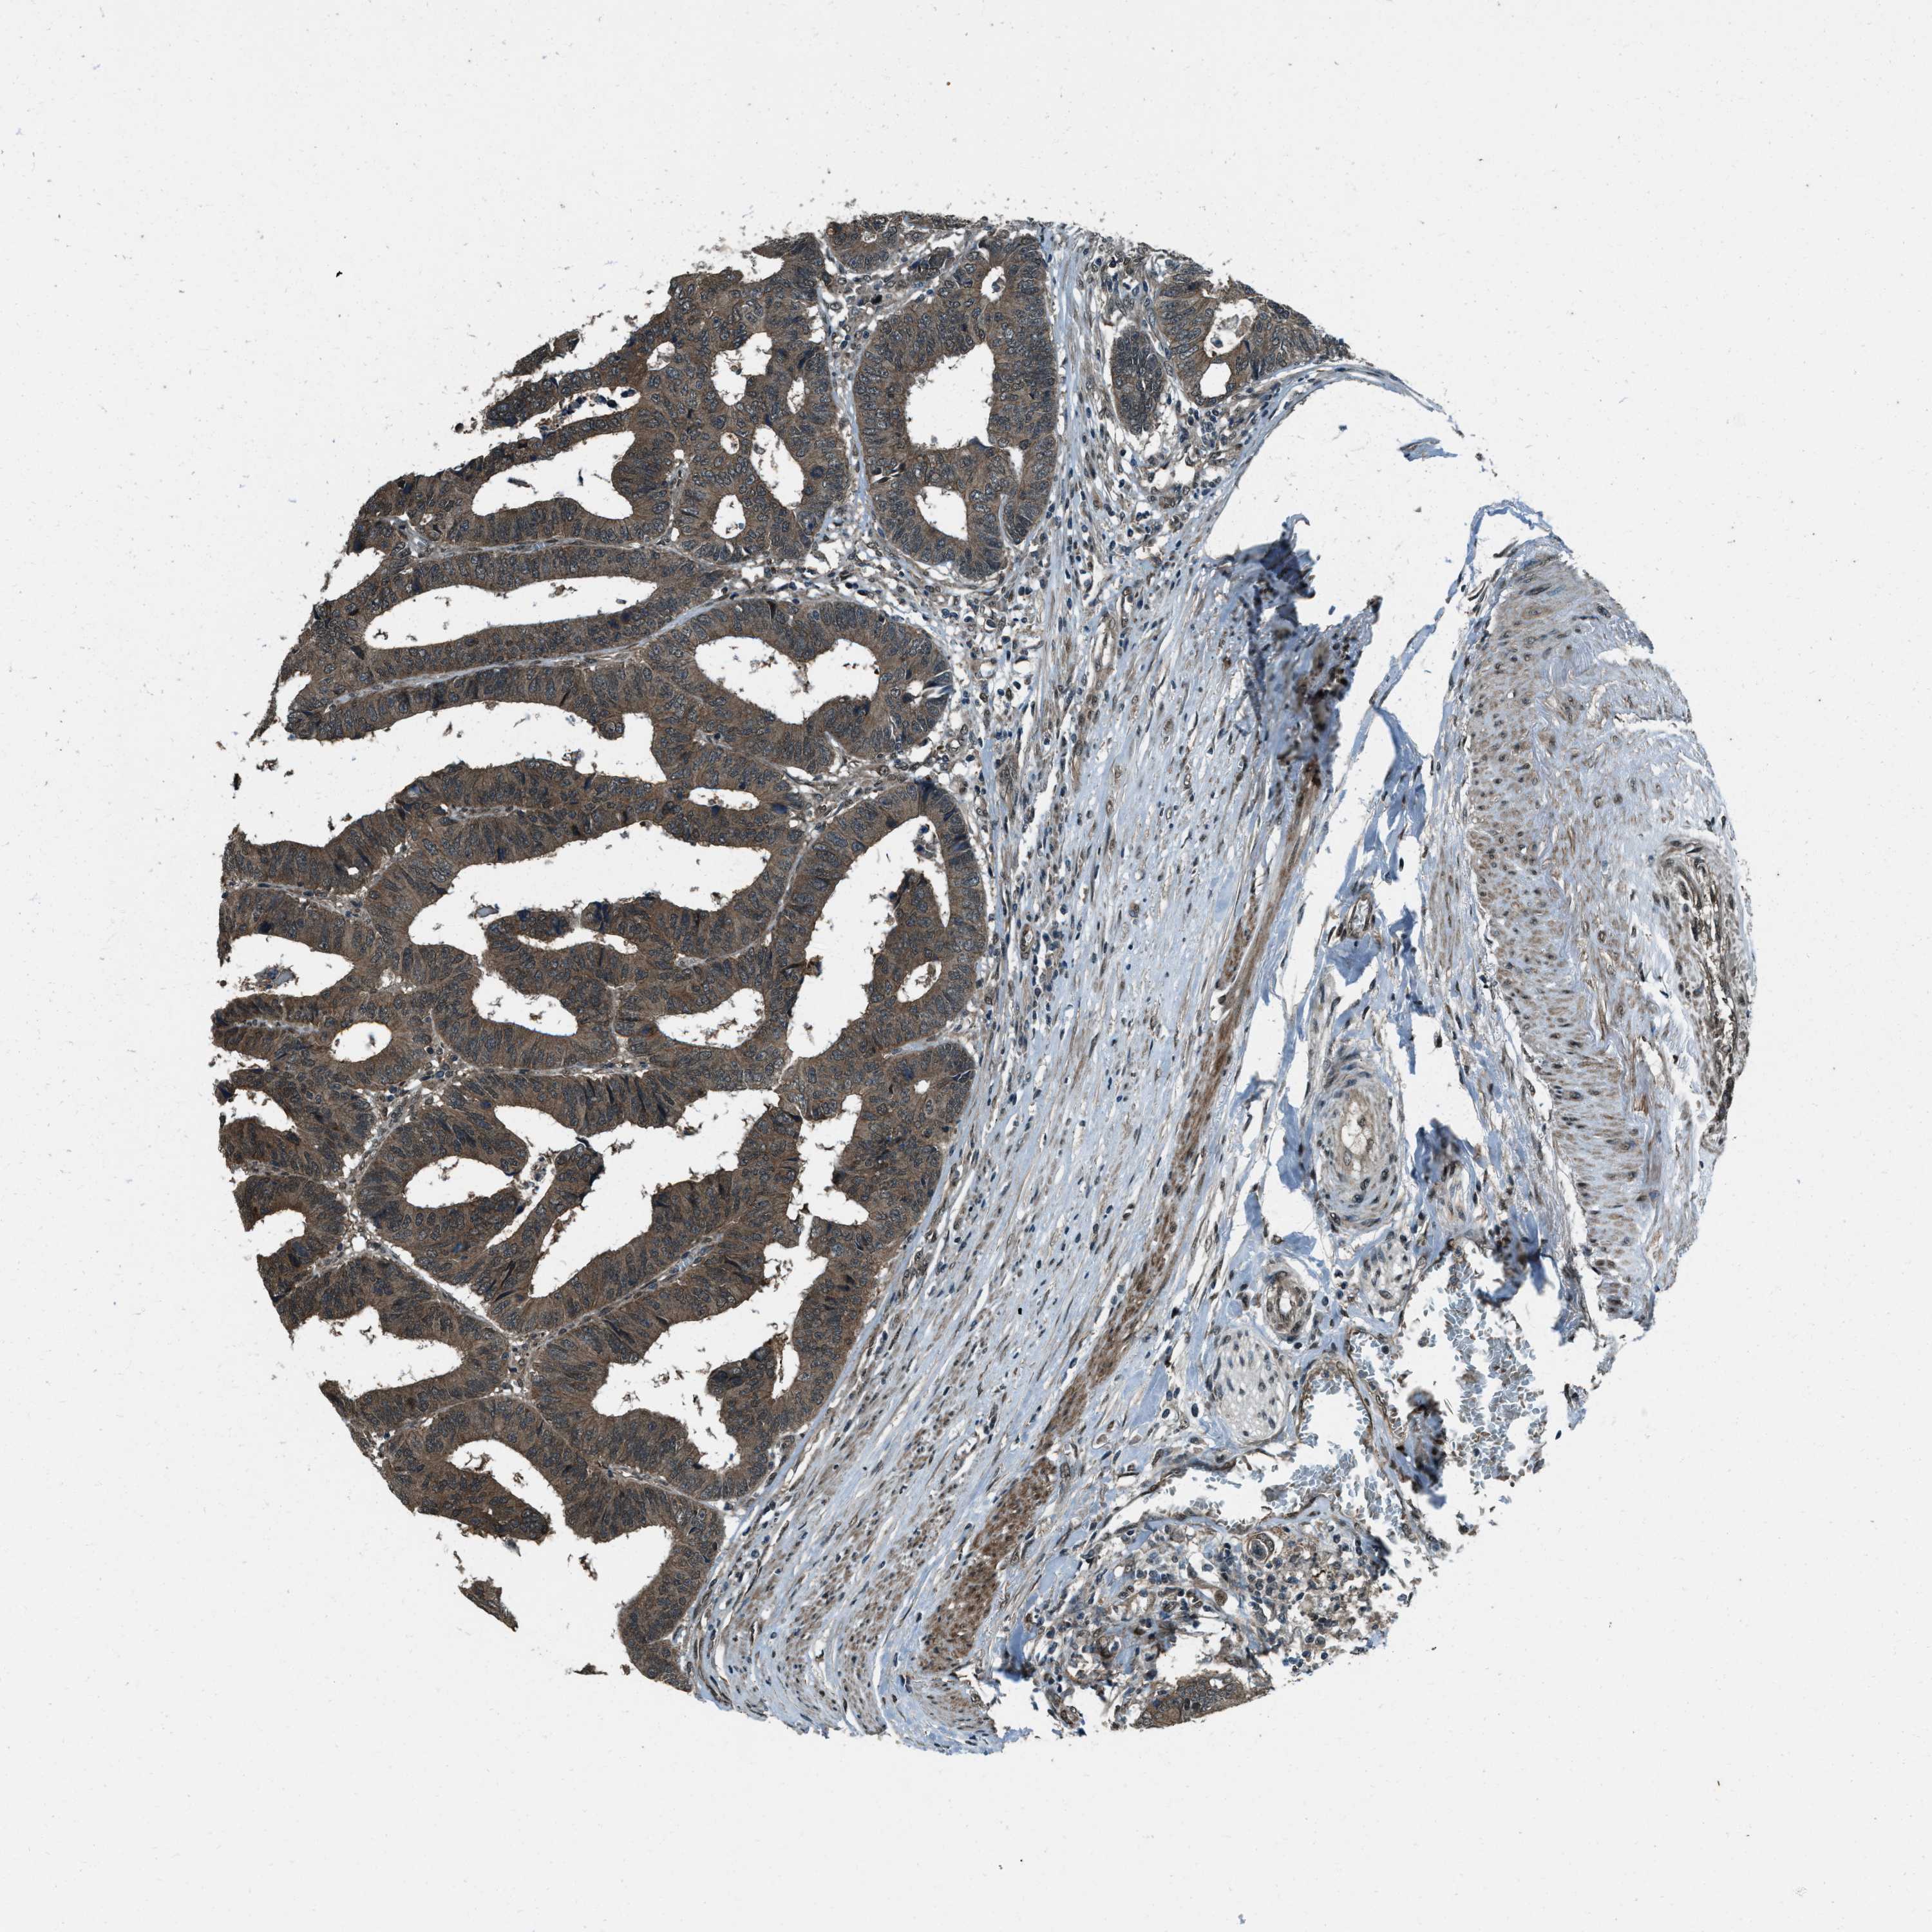

CANCER COLORECTAL CANCER Show tissue menu

Colorectal cancer

Human cancer

Colon adenocarcinoma